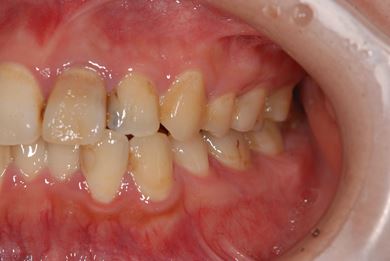

治療前

• 治療前